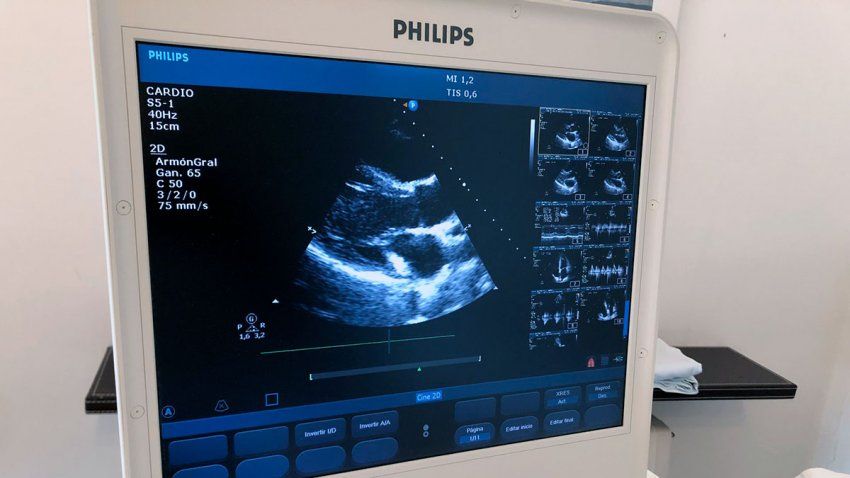

A través de un ecocardiograma obtenemos imágenes detalladas del corazón, permitiéndonos evaluar su estructura y función y, con ello, diagnosticar posibles afecciones...